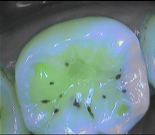

Why is the tooth green on the screen?

The spectrum of the signal of fluorescence (let’s call it "its color") is rather in the green when the dentine is healthy and red/dark when the dentine is infected.

What represent the white, blue, red or black areas which can been seen on the tooth?

According to the pathologies of the tooth (destructured enamel, affected dentine, anfractuous fissure, presence of a crown…), the signal of fluorescence of the dentine will be different (weaker, darker, redder, absent…)